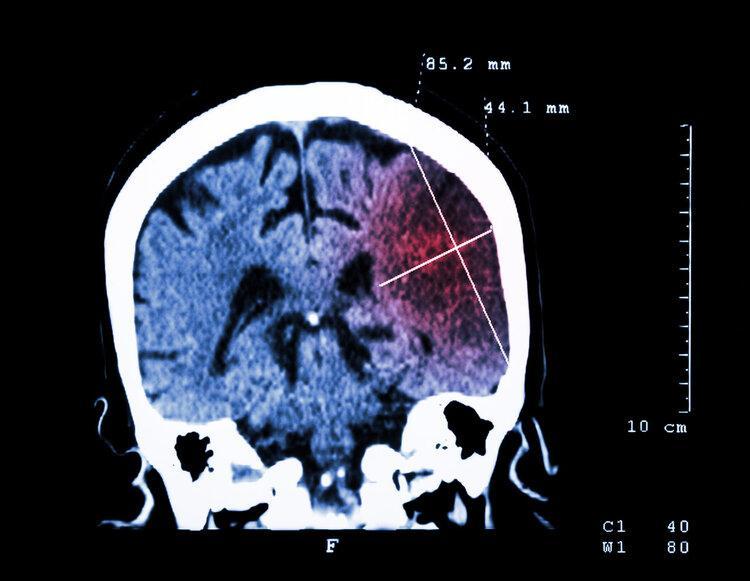

腦梗也就是急性腦梗死,是腦部斑塊侵蝕以及血供不足後,造成腦組織缺血、腦細胞損傷和死亡的一種腦部疾病,具有危險性高且後遺症嚴重等特點。